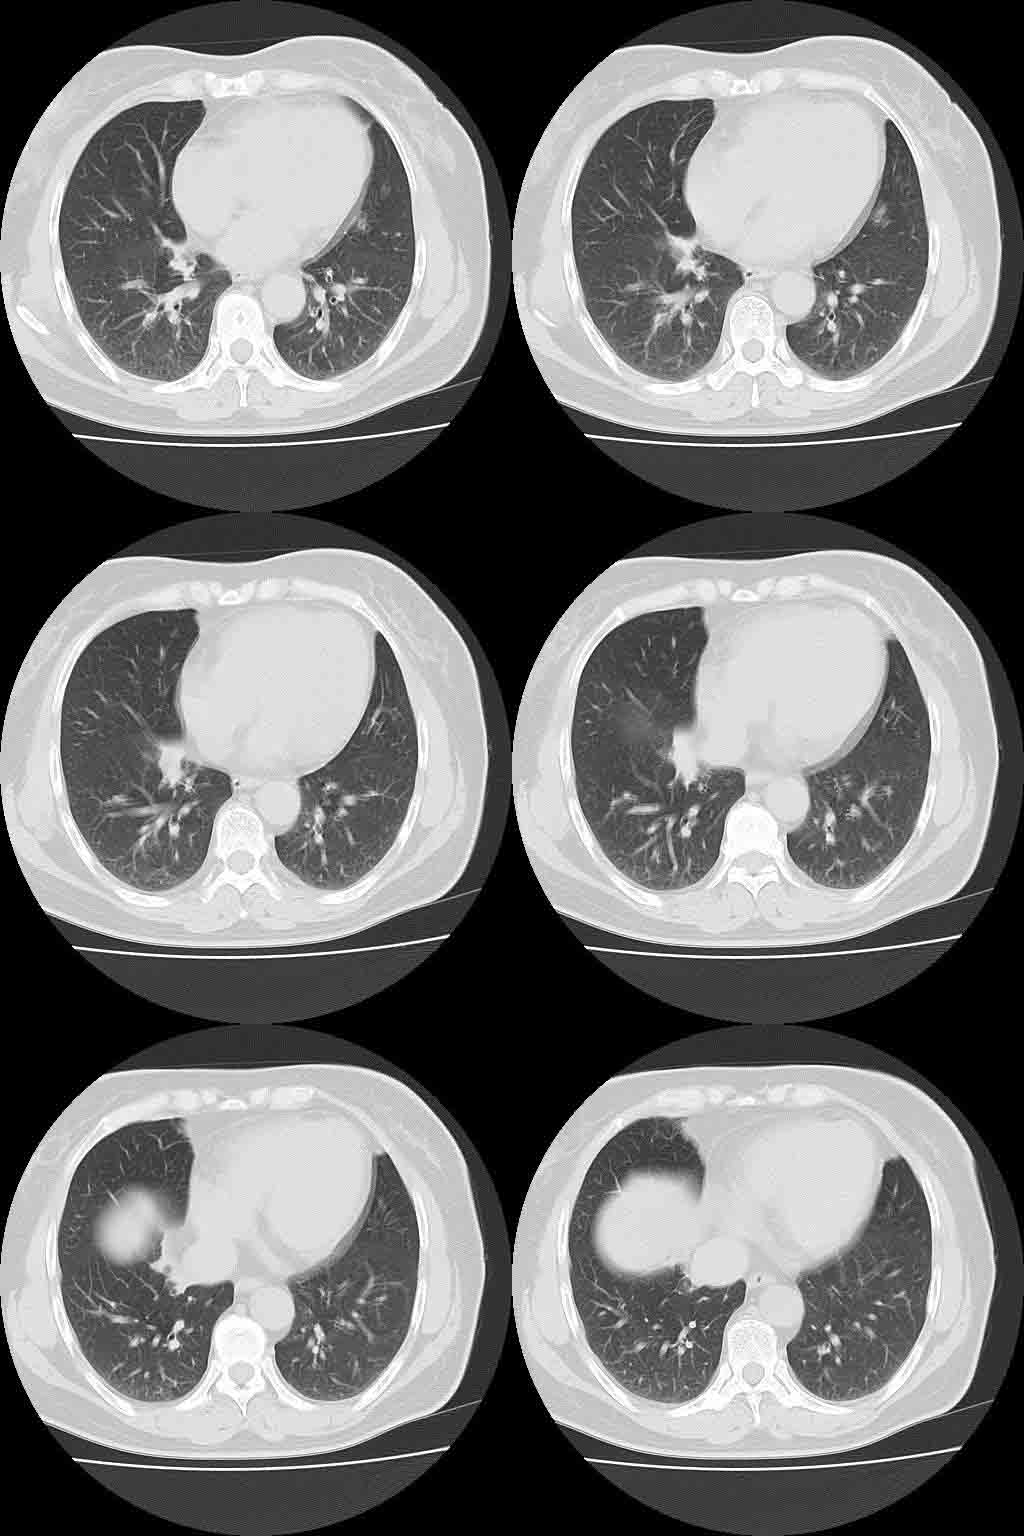

以下是引用lkc8963在2008-10-4 22:24:00的发言:[br]右下肺内基底段不规则软组织结块,肿瘤可能,建议增强鉴别于血管.